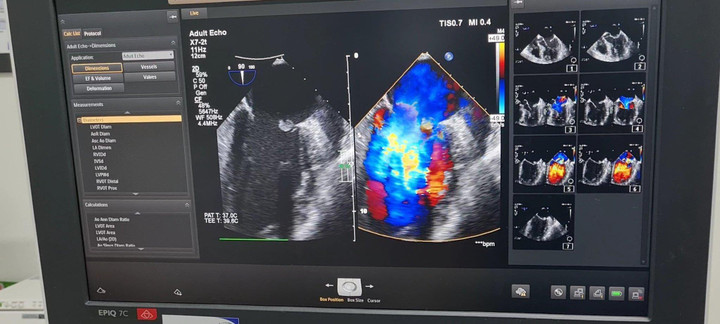

Siêu âm tim anh T phát hiện cục sùi lớn, gây thủng van và làm hở nặng van hai lá.

Ths Lưu Quang Minh, khoa Hồi sức tim mạch, Bệnh viện Trung ương Quân đội 108 cho biết, ban đầu là vết thương khớp gối nhiễm khuẩn, vi khuẩn (thường là tụ cầu hoặc liên cầu) theo máu đến tim, gây viêm màng trong tim nhiễm khuẩn, với tổn thương điển hình là các cục sùi bám trên các lá van tim. Khi kích thước cục sùi lớn, một phần bong ra và theo máu đến các cơ quan, trong đó có mạch máu nuôi ruột, gây bít tắc và thiếu máu, hoại tử ruột. Trên thế giới, các trường hợp tắc mạch ruột do viêm màng trong tim nhiễm khuẩn thường rất hiếm.